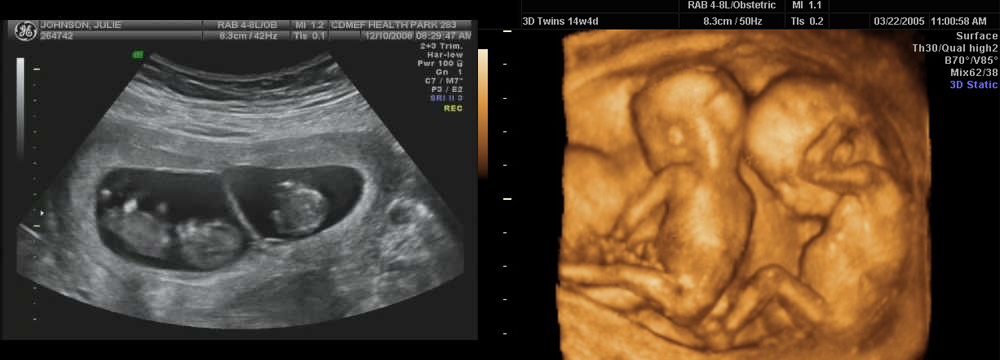

Развитие эмбриона на 8 неделе беременности